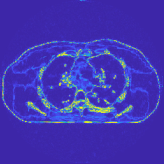

This section compares the reconstruction quality and runtime among the proposed MBIR method, PWLS-ST-, and other three MBIR methods, PWLS-EP, PWLS-DL, and PWLS-ST-. Table I shows that, for both 2D and 3D sparse-view CT reconstructions of the XCAT phantom, the proposed PWLS-ST- model outperforms PWLS-EP and PWLS-ST- in terms of RMSE. In addition, PWLS-ST- using a square transform (of size ) achieves lower RMSE than PWLS-DL using an overcomplete dictionary (of size ) for 2D sparse-view reconstructions. Fig. 3(a) and Fig. 4 show the reconstructed images for 2D and 3D phantom experiments, with different reconstruction models and different number of views. (See the corresponding error maps in the supplement.) The proposed PWLS-ST- consistently gives more accurate image reconstructions compared to other MBIR methods. Specifically, PWLS-ST- has smaller errors in the heart region (see zoom-ins in Fig. 3(a)) of 2D reconstructions than PWLS-DL and PWLS-ST-. In addition, compared to PWLS-ST-, PWLS-DL and PWLS-ST- have some ringing artifacts around the edges with high transition, e.g., edges between air and soft tissues. (See a comparison of profiles of PWLS-ST- and PWLS-ST- in the supplement.) In particular, PWLS-ST- and PWLS-DL give more visible ringing artifacts for 2D reconstruction from fewer views, and PWLS-ST- has these ringing artifacts for 3D reconstructions regardless of the number of views (see zoom-ins in Fig. 4). Table II reports runtimes of different MBIR methods in reconstructing the -views XCAT phantom scan. (FBPConvNet is a non-MBIR method and its runtime for processing a image is approximately one second with a TITAN Xp GPU.) While providing better reconstruction quality, the proposed Algorithm 1 of PWLS-ST- has shorter runtime compared to the algorithms of PWLS-DL and PWLS-ST- in Section III-A. Similar to the PWLS-EP algorithm, the reconstruction time of the PWLS-DL, PWLS-ST-, and PWLS-ST- algorithms can be further reduced by using ordered subsets [51].

The benefit of the proposed PWLS-ST- over PWLS-ST- can be explained when there exist some outliers for some : in (12) gives equal emphasis to all sparse codes – from small to large coefficients that generally correspond to edges in low- and high-contrast regions, respectively – in estimating ; however, PWLS-ST- adjusts to mainly minimize the outliers, i.e., it may not pay enough attention to reconstruct regions with small coefficients. The histogram results in Fig. 1 reveal model mismatch of PWLS-ST- over the iterations. Fig. 3, Fig. 4, and Table I show that PWLS-ST- can moderate model mismatch, and provides more accurate reconstruction than PWLS-ST-.

| views | ||||

| (a) , | (b) , | (c) , | (d) , |